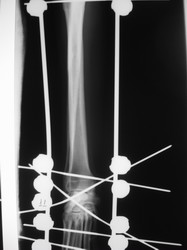

PRÁCTICAS CURSO DE FIJACIÓN EXTERNA PERFECCIONAMIENTO.

Artrodesis carpo.